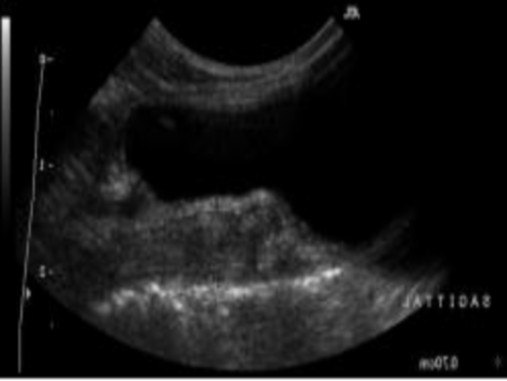

Hình 2.13. Ảnh mặt cắt thẳng đứng ở chính giữa

của thân tử cung trong giai đoạn sau động dục (con trỏ)

Chú thích: Dưới tác động của progesterone, niêm mạc tử cung dày lên, phản ánh sự phát triển của tuyến, ít chất lỏng có mặt trong lòng tử cung. Tử cung sẽ dày nhất trong thời gian không động dục.

Nguồn: Rachel Pollard & Silke Hecht (2015)